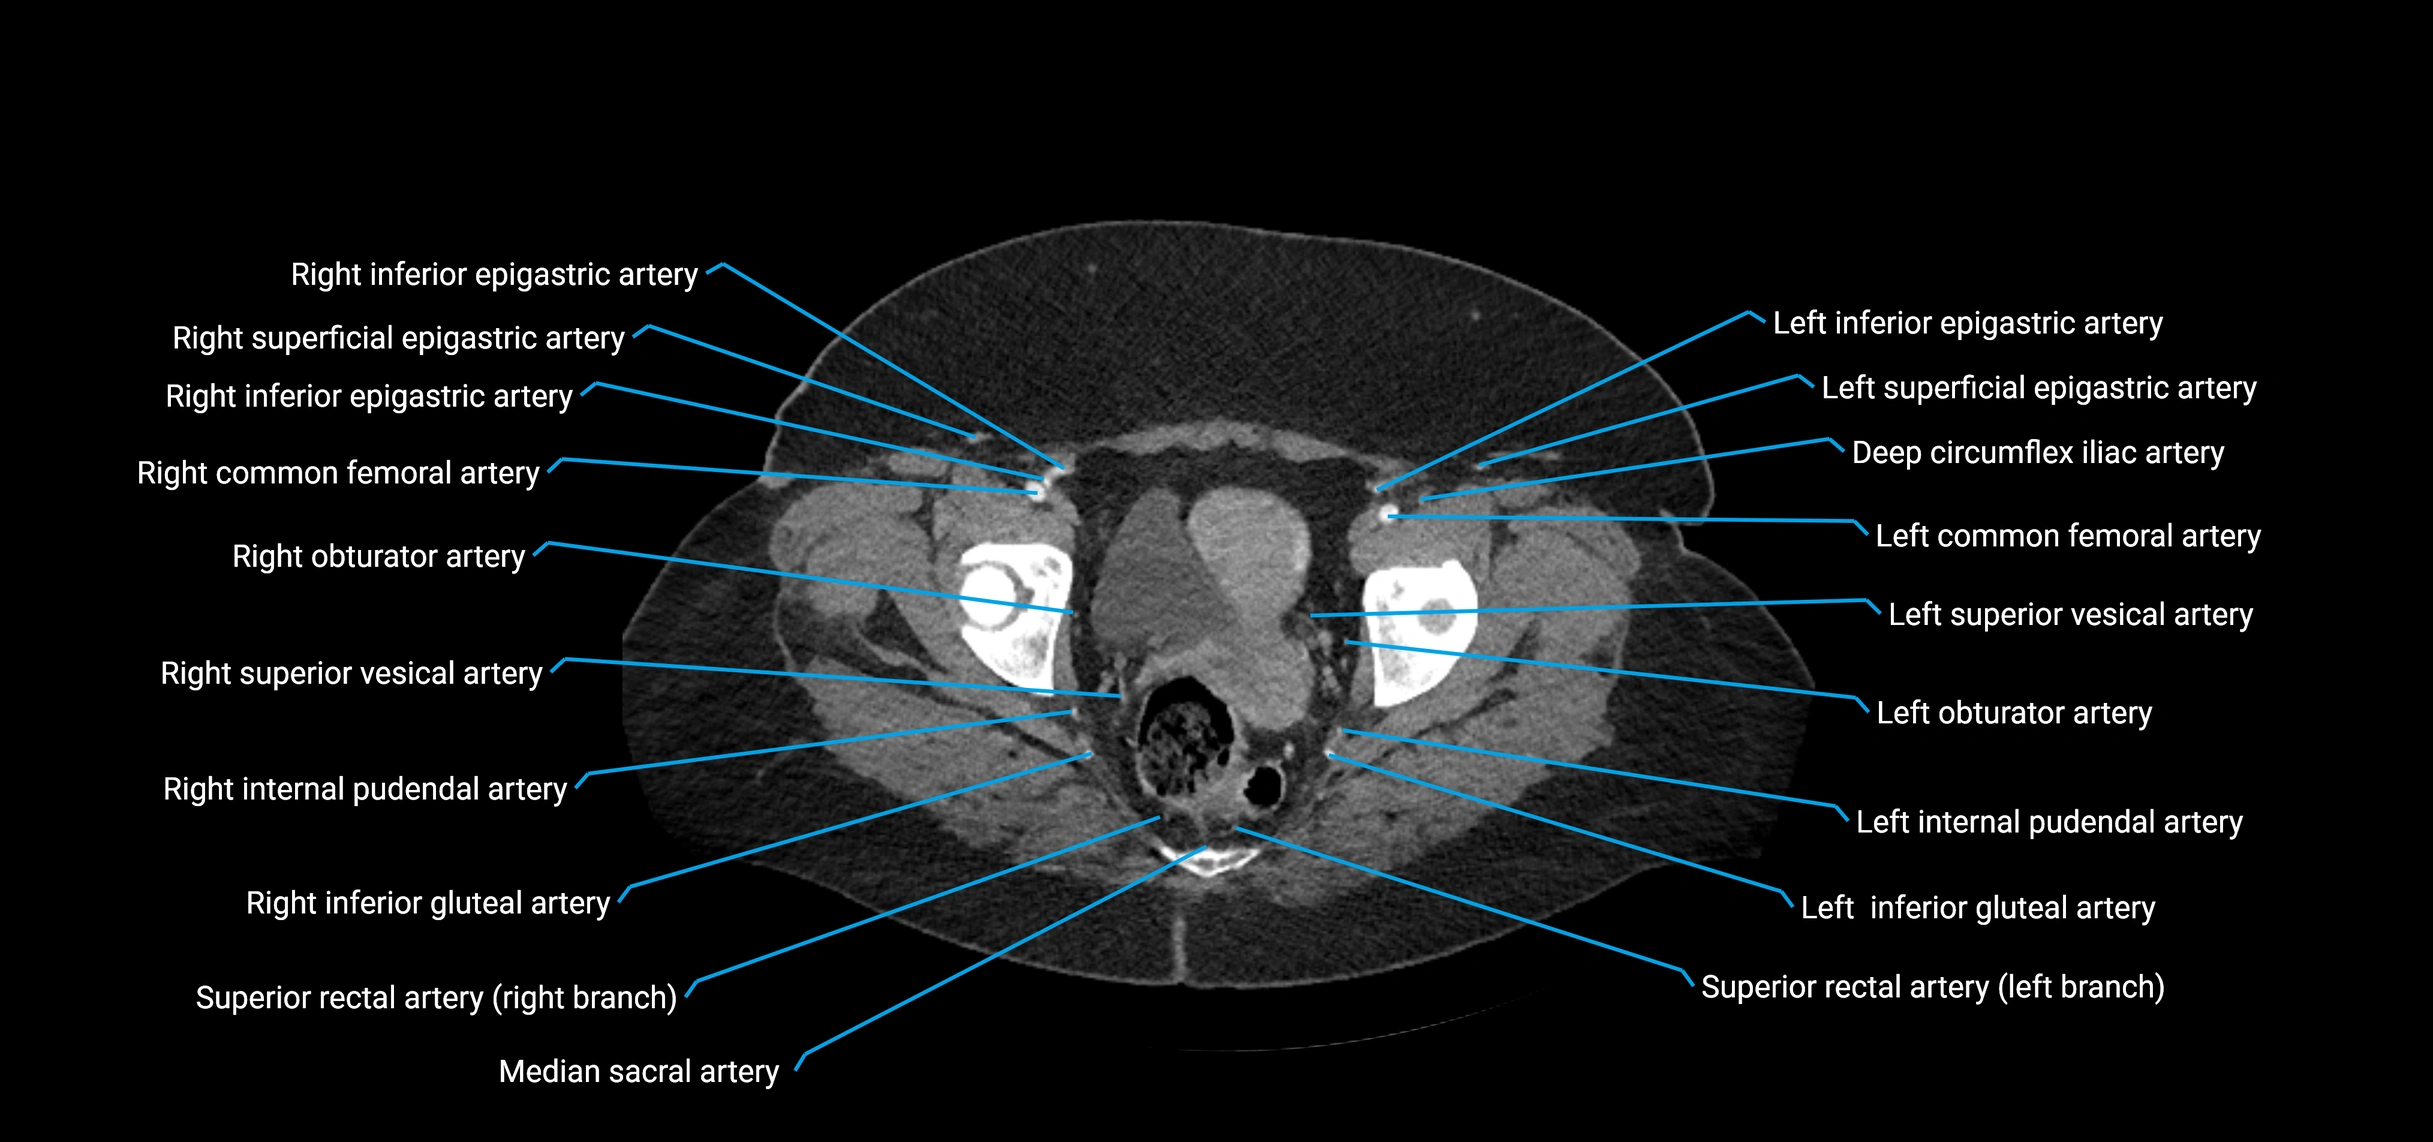

Contrast-enhanced CT (CTA):

• Gold standard for abdominal aortic imaging

• Provides excellent detail of lumen, wall, aneurysm, thrombus, and branch vessels

• Multiplanar and 3D reconstructions help in aneurysm measurement, stent graft planning, and dissection evaluation

• Detects acute rupture, traumatic injury, or occlusion with high sensitivity